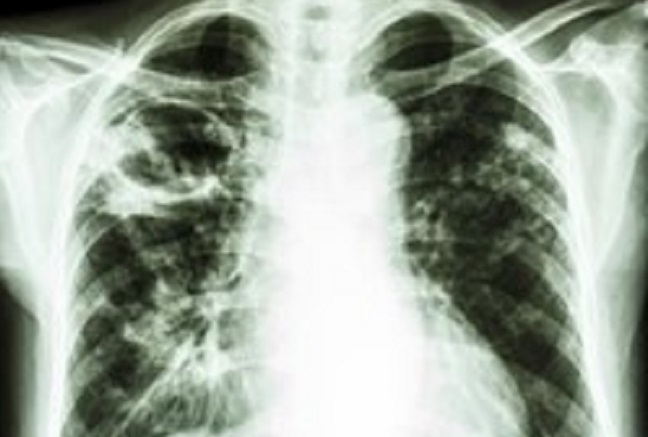

Kavitas paru secara radiologi didefinisikan sebagai area yang lusen di dalam konsolidasi, massa, atau nodul. Kavitas biasanya dibatasi dengan dinding tebal yang diameternya lebih dari 4 mm. Sementara itu, Fleischner glossary mendefinisikan kavitas sebagai ruang yang diisi gas, terlihat sebagai area lusensi atau atenuasi rendah di dalam konsolidasi, nodul, atau massa. Contoh gambaran lesi kavitas dapat dilihat pada Gambar 1 di bawah ini.[1-3]

Gambar 1. Lesi Kavitas pada Lapangan Atas Paru Kanan

Kavitas paru harus bisa dibedakan dengan kista, di mana area lusen pada kista tidak dikelilingi konsolidasi, massa, atau nodul, serta memiliki dinding yang lebih tipis.[2]